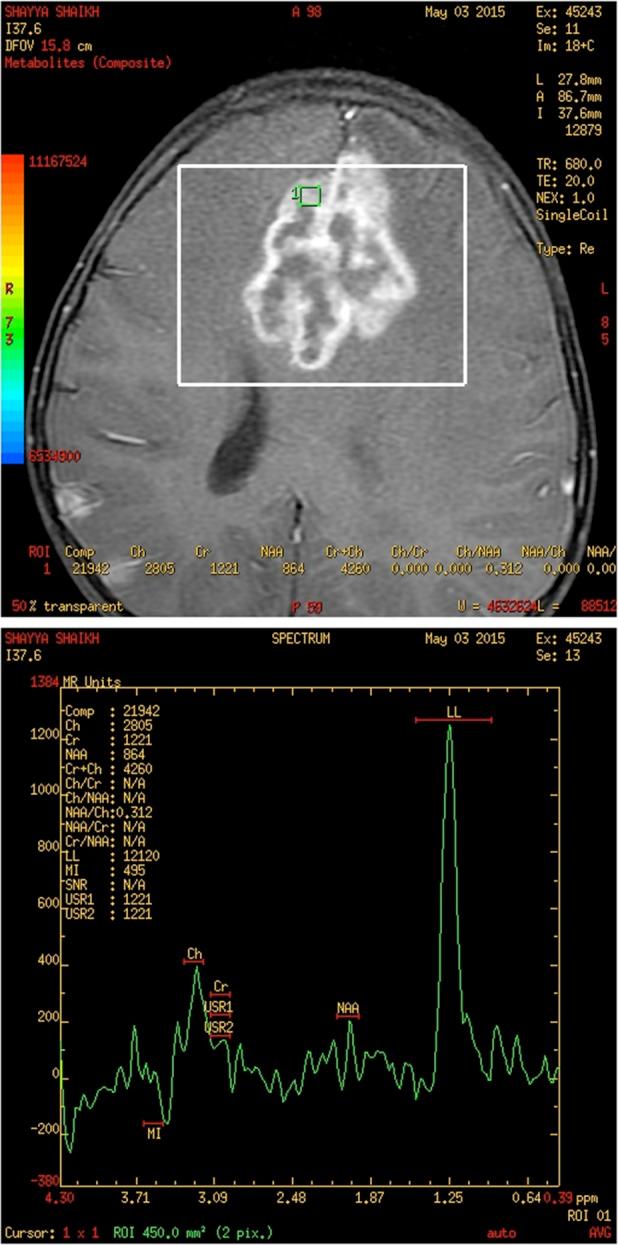

Tuberculomas are usually infratentorial in children, and supratentorial lesions predominate in adults. We present a 4-year-old girl with multiple seizures, papilloedema and brisk reflexes. On investigation, she was found to have a large left parafalcine tuberculoma. She was treated with antitubercular treatment (ATT) and steroids. The child improved, seizures stopped and the papilloedema gradually disappeared. Follow-up magnetic resonance imaging brain after 8 months showed a mild reduction in the size of the lesion. Child is on regular follow-up.